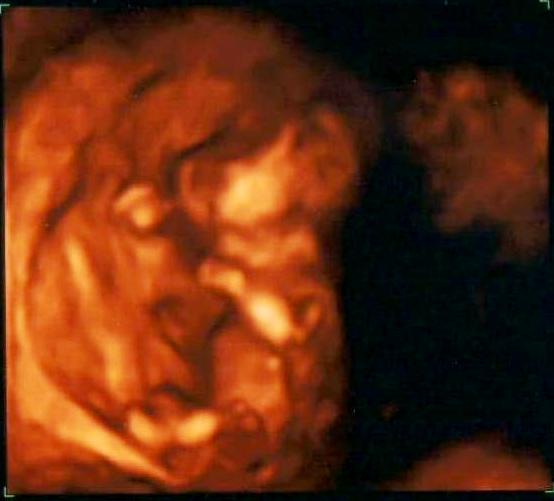

Je fajn, že jste si to oba užili, i když teda mrňous spolupracoval je napůl - že se nechal v klidu změřit:) a s viditelností pohladí je to asi u každého jinak, já počítám, že vzhledem k tomu, že třeba já jsem "objemnější", tak drobnosti budou vidět až na dalším UTZ nejdřív:) Dávám tu obrázek toho našeho kulíška, kus hlavy mu nechybí, i když to tak vypadá...:)

[320068] hezka fotka miminka :-) Nam udelali pouze 2D vysetreni,takze zadnou takovou "realnou" fotku nemam :-( Ale i na tim 2D utz byli mimi pekne videt. A ty cekas sve prvni miminko? Nebo uz mate nejake to ditko doma?:-) Jinak proporce pred tehotenstvim jsem mela 58kg/172cm. Mam ted 2kg nahore a bricho je mi tak videt,ze uz se me znami na ulici ptaji,jestli nejsem tehotna.Uplne me sokovalo,jak to jde rychle :-D a to jsem teprve 12+6tt :-O Lucie- vítej v diskusi :-) cisar ma i sve vyhody - aspon dopredu vis,kdy to bude s jak to bude :-). Ja tezce nesu nejistotu a zmeny,takze pro me je tehotenstvi na jednu stranu radost,na druhou i stres ;-) sama jsem se narodila cisarem a vse bylo ok. Uzivej si tehulkovani ;-)